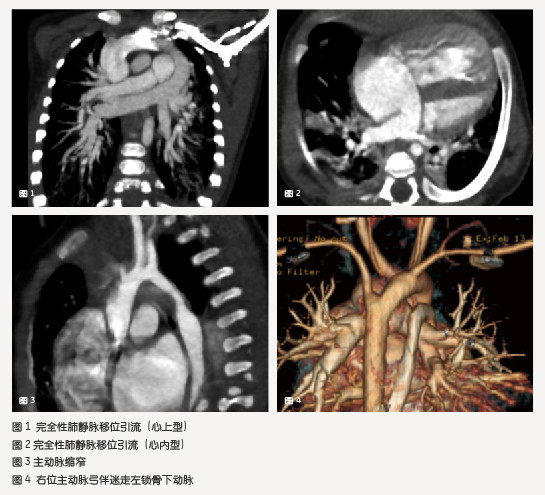

结果:常规组与对照组在主动脉、肺动脉、肺静脉、左右心腔、上下腔静脉、支气管的显示方面无明显差异,在形态学诊断方面均能满足临床诊断的要求,在观察心内分流方面无明显差异。改进组降低了对比剂的使用剂量,减少了对比剂进入上腔静脉前的空扫次数,减弱了上腔静脉对比剂的伪影,减少辐射剂量,从总体上提高了螺旋穿梭的使用效率。

结论:在使用螺旋CT低剂量动态500排技术诊断小儿先天性心脏病时,通过改进对比剂使用剂量计算方法、注射时间、注药速度及控制扫描床穿梭次数等因素,达到以最小对比剂量、最低辐射扫描并正确诊断的效果是可行的。